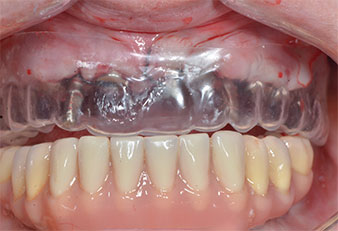

Three years later it was time for a maxillary denture of the same type. Based on CBCT planning sinus augmentation was avoided with the aid of short implants, and a surgical template was used to transfer the planned positions to the alveolar ridge (Figs. 1 and 2).

Fig. 1: Pre-operative view of the maxillary ridge, with implant positions marked with the aid of a surgical plastic template. Due to the low ridge super short posterior implants are planned.

Implant positions